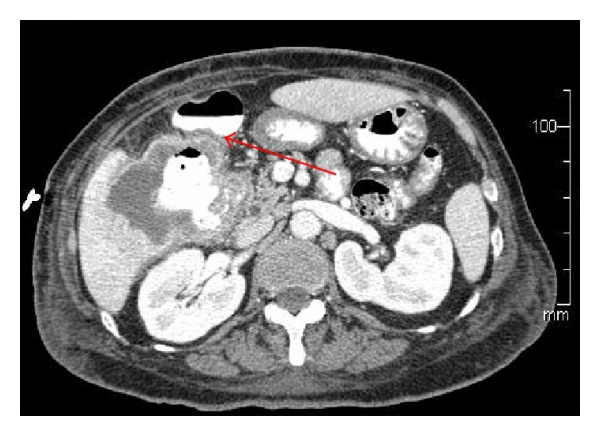

A 67-year-old Asian female presented to her primary care physician in March 2012 with persistent fever and chills with associated weakness and weight loss. She had no abdominal symptoms or history of gallbladder pathology. She was treated for bronchitis but her fever and chills persisted despite multiple rounds of oral antibiotic therapy. Further workup revealed a leukocytosis of 30,000 wbc/μL. She underwent hematology/oncology evaluation to exclude a possible bone marrow dysplastic process. This did not demonstrate an underlying cause for the leukocytosis. She presented to a local emergency room in mid-June 2012 with complaints of chills, weakness, and malaise. She was admitted with Gram-negative rod bacteremia. A computed tomography (CT) scan was obtained which demonstrated an 8.6 cm mass of the right lobe of the liver with associated abscess (Figure 1). Biopsy of the lesion revealed SCC of the gallbladder (Figure 2). Percutaneous drainage of the abscess was performed which was significant for E. coli and Enterococcus. She was discharged on antibiotic therapy but readmitted ten days later with fever, chills, and failure to thrive. Repeat CT scan imaging revealed an increase in the size of the mass to 10.2 cm. Evidence of fistulization of the lesion to the gastric antrum, duodenum, and hepatic flexure of the colon was also noted (Figures 3 and 4). There was no distant metastasis or lymphadenopathy observed. She was referred to our institution in August 2012 for consideration of additional therapy. Magnetic resonance imaging revealed her tumor to be potentially resectable. However, because of her limited reserve and declining functional status, it was felt that she may not tolerate radical en bloc resection. Palliative chemotherapy was offered but declined. Comfort care measures were recommended and the patient passed away soon thereafter.